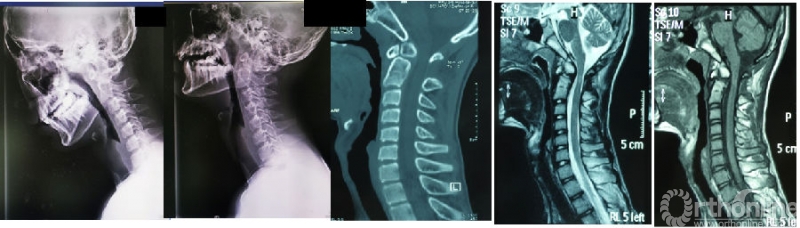

图5:男性22岁;术前诊断齿突不连、寰枢椎不稳定、高位颈脊髓病(脊髓高信号)

图6:采用中线切口、显微镜辅助下双侧经肌肉间隙入路、保留伸肌张力带;侧块间植入棘突骨(避免取髂骨);肌肉间隙内行寰枢椎椎弓根钉棒固定

图7:术后第一天出院,切口VAS评分仅为2分;术后4月复查可见寰枢椎解剖复位、侧块间骨融合牢固;脊髓压迫完全解除。